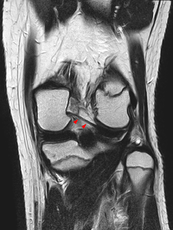

Posterior meniscofemoral ligament on MRI, coronal

The Posterior meniscofemoral ligament is a small fibrous band of the knee joint. It attaches to the posterior area of the lateral meniscus and crosses superiorly and medially behind the posterior cruciate ligament to attach to the medial condyle of the femur.

Posterior meniscofemoral ligament (Wrisberg) behind the posterior horn of the lateral meniscus close to its insertion. Sometimes wrongly interpreted as a meniscal tear.